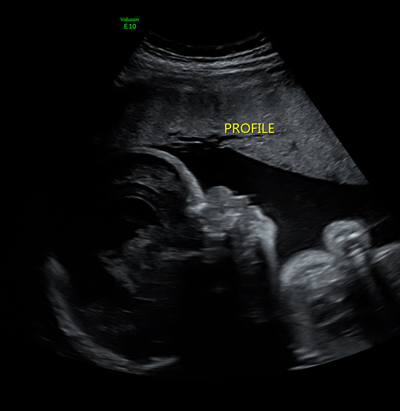

What is this image showing?

Thanatophoric Dysplasia